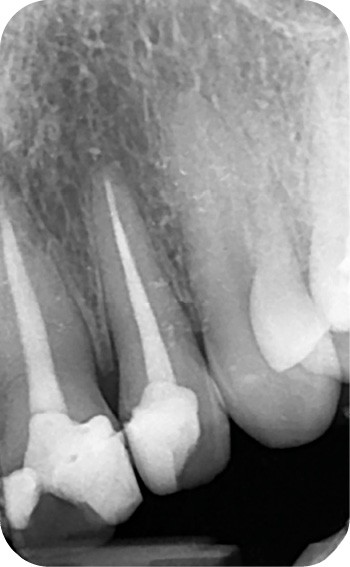

– Iatrogène (à la suite de traitements endodontiques ou à l’amalgame d’argent) (fig. 6a, b).